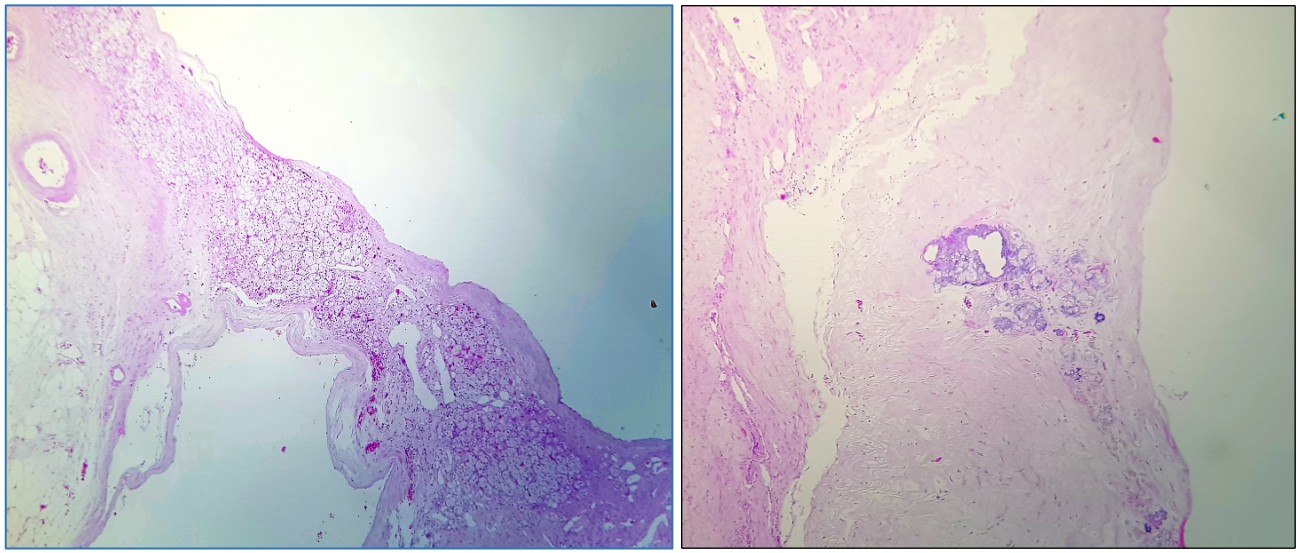

Pieza quirúrgica sin fijar, superficie exterior (izquierda)y al corte (derecha)

Pieza quirúrgica al corte fijada